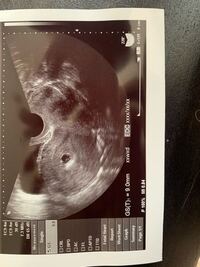

5週 胎嚢 大きさ 9ミリ-5ミリ(胎嚢に線のようなものが見える)(a秒) 6月21日胎嚢7~8ミリ(白い点が見える)(b病院) 大きさ的に小さく、6月25日に心拍確認出来なければほぼ流産と言われてしまいとても不安です。 1度妊娠5週相当胎嚢の8ミリ卵黄囊確認済で自然流産の経験があります。妊娠4週目 約15mm 妊娠5週目 約1cm 妊娠6週目 約15~2cm 妊娠7週目 約25~3cm

5週で6.2ミリ 6週で12.5ミリ(卵黄嚢はみえる)→流産となりました。 私の中では排卵にずれがない場合(あっても2.3日)は 数日胎嚢の大きさが小さいのは大丈夫として 10日以上遅い、一日一ミリ大きくなるこの時期に 一週間で5ミリ以下しか大きくなっていない場合は あまりよくないかなと思い 5週の胎嚢サイズ→10~25mm 6週の胎嚢サイズ→15~30mm 7週の胎嚢サイズ→~37mm 胎嚢サイズの目安については以上。 自分の実際の胎嚢サイズと 照らし合わせてみると、 ※経過が分かりやすいように 心拍確認できるまでの結果を 先に載せてしまいます。 4w6d 目